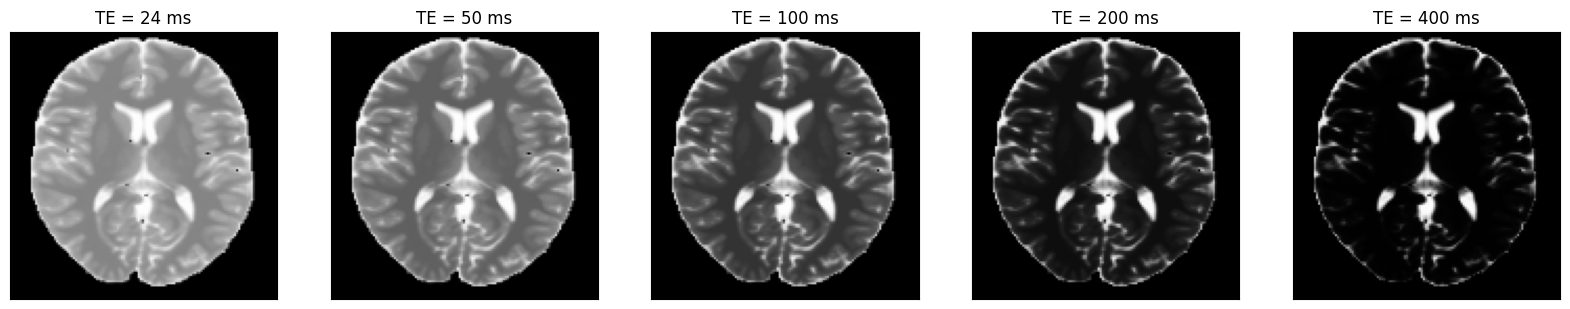

We can now plot the images at different inversion times.

idat = idata.data.abs().numpy().squeeze()

fig, ax = plt.subplots(1, idat.shape[0], figsize=(4 * idata.shape[0], 4))

for i in range(idat.shape[0]):

ax[i].imshow(idat[i, :, :], cmap='gray')

ax[i].set_title(f'TE = {int(idata.header.te[i] * 1000)} ms')

ax[i].set_xticks([])

ax[i].set_yticks([])

_images/20fc262f63e2a8daa3eac9fd60d80aacbaa020ec28aacafae90131a1f5ba53ea.png